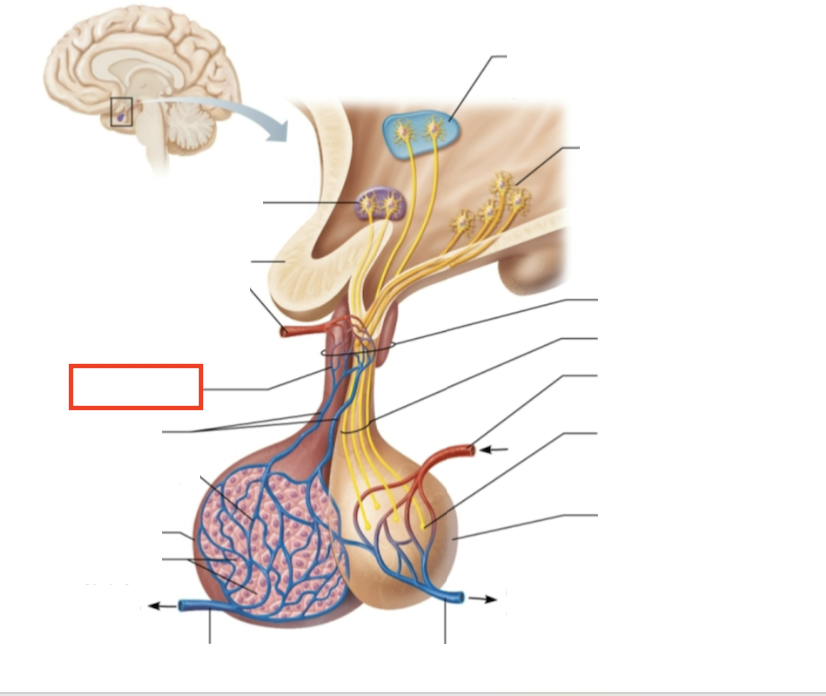

What structure is highlighted?

testes (male)

What structure is highlighted?

hypothalamic neurons in the paraventricular nuclei

What structure is highlighted?

neurons in the ventral hypothalamus

What structure is highlighted?

infundibulum (connecting stalk)

What structure is highlighted?

hypothalamic-hypophyseal tract

What structure is highlighted?

inferior hypophyseal artery

What structure is highlighted?

neurohypophysis (storage area for hypothalamic hormones)

What structure is highlighted?

posterior pituitary

What molecules are produced here?

oxytocin, ADH

What structure is highlighted?

venule

What structure is highlighted?

venule

What molecules are produced here?

TSH, FSH, LH, ACTH, GH, PRL

What structure is highlighted?

secretory cells of adenohypophysis

What structure is highlighted?

anterior pituitary

What structure is highlighted?

secondary capillary plexus

What structure is highlighted?

hypophyseal portal veins

What structure is highlighted?

primary capillary plexus

What structure is highlighted?

superior hypophyseal artery

What structure is highlighted?

superior hypophyseal artery

What structure is highlighted?

optic chiasma

What structure is highlighted?

hypothalamic neurons in the supraoptic nuclei